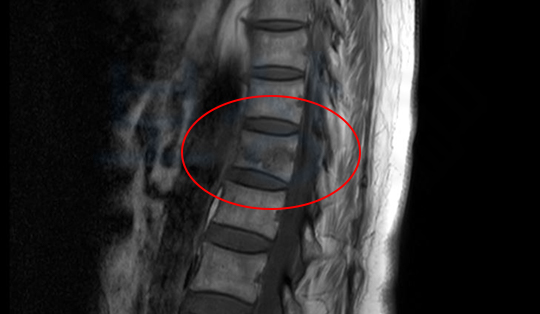

병원 진료 결과, 제12흉추골 골절 진단을 받으셨죠. (흉추 12번 골절)

이 경우에는 상태가 심한 상황은 아니었기 때문에 수술적인 치료 없이 척추 TLSO 보조기를 착용하시며 몇개월간 안정이 필요하였습니다.

척추의 뚜렷한 장해 (30%) 영구장애

진단을 받게 되었습니다 이를 기초로 손해사정서를 작성하여 각 보험사에 청구하게 되었고, 후유장해 보험금 총 2,100만원을 받으실 수 있었습니다.